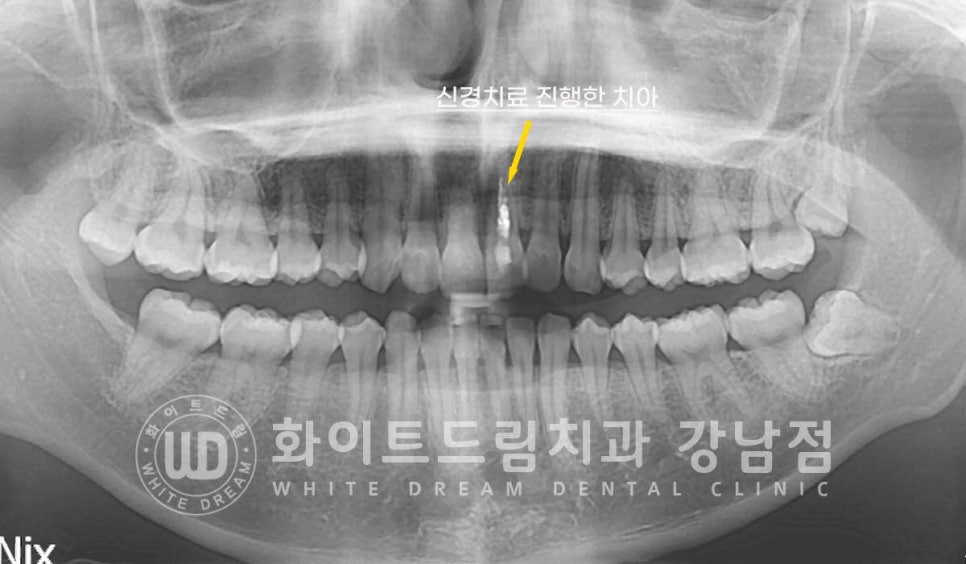

신경치료를 받은 치아는 내부 혈관과 신경이 제거된 상태로

자연치아에 비해 굉장히 약한 상태입니다.

그래서 보통 신경치료 후 크라운 치료를 진행해 약해진 치아를 보호해 주게 되는데요.

전치부 치아들은 일상생활 중에 교합압이 거의 작용하지 않기 때문에

이렇게 신경치료만 진행한 후에도 크라운 치료를 따로 진행하지 않는 경우들이

많습니다.

신경치료를 받은 치아, 왜 변색이 될까요?

신경치료는 앞서 말씀드린 대로 신경과 치아 내부 혈관을 모두 제거하는 진료입니다.

신경치료를 진행하는 과정에서 내부 출혈이 발생할 수 있는데

치료 후 남아있던 적혈구들이 변색이 되면서 겉으로 비춰 보이는 경우가 흔합니다.

혹은 신경치료 시 사용되는 재료들에 의해 변색이 일어날 수도 있답니다.